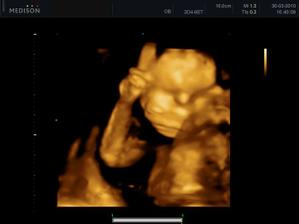

11.05. - (26+5) dnes jedeme na video

video se povedlo, máme asi 6 cca 5 - 10ti vteřinových videíí.Bylo to super. Karolínka se zase mlela jako drak. Je taková živoučká 😀